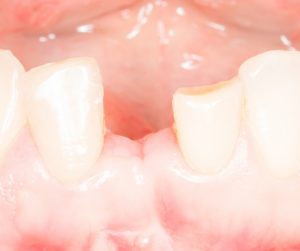

Рекомендации по установке имплантов. Для всех. Часть V.